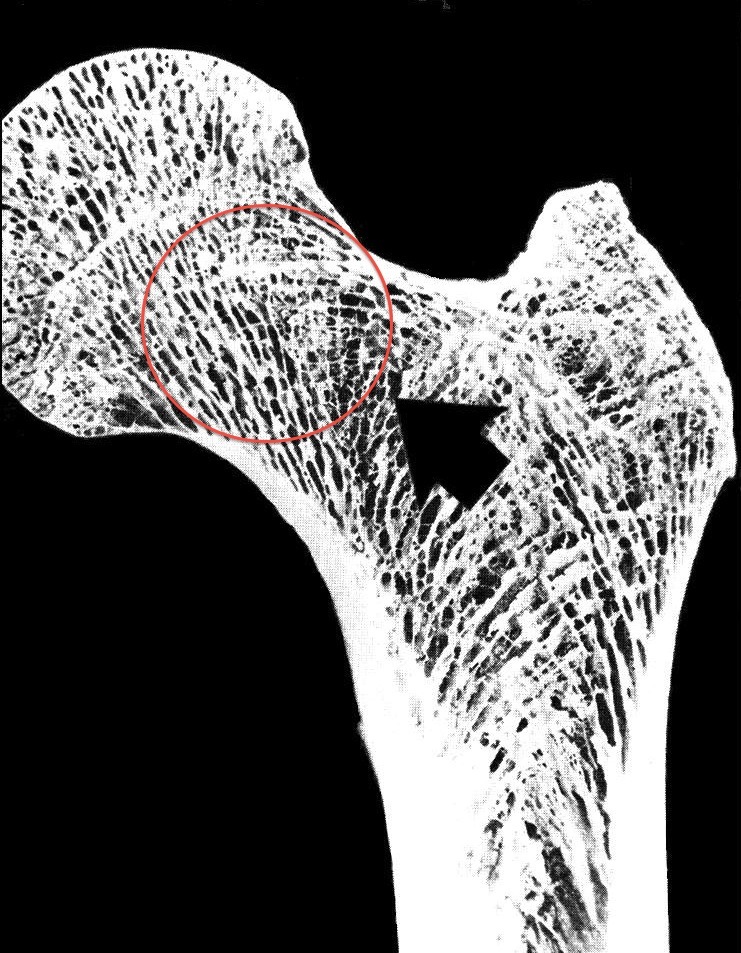

Identify the circled structure.

Osteocyte in lacuna